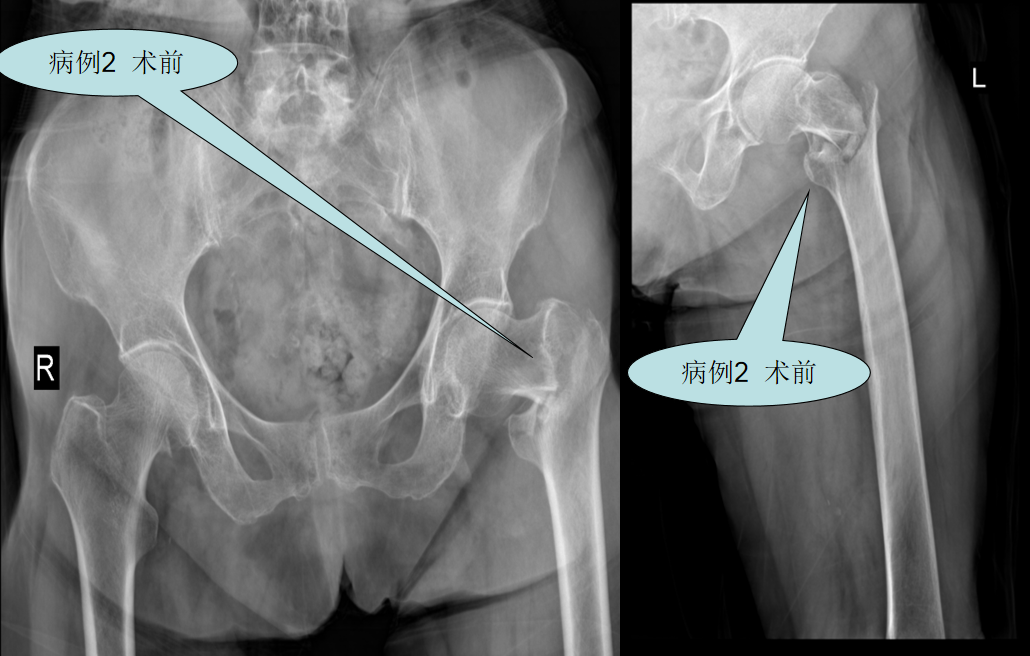

【病例二】